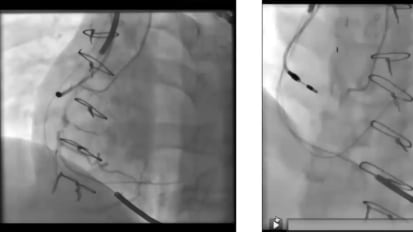

In this engaging interview, Anjali T. Owens, MD, discusses the inherited cardiomyopathies, and research in genetic sequencing as a precedent for the development of targeted therapies for the disorder at the Perelman School of Medicine. Dr. Owens is the Medical Director for the Center for Inherited Cardiac Disease at Penn Medicine.